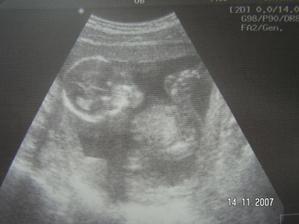

Tak jsme zpět z poradny.Jestli to bude kluk nebo holčička nevíme,protože miminko překřížilo nožky a nechtělo se ukázat.Za to na mamku krásně mávalo,tak to pan doktor zvěčnil-fotka je v albíčku.Měříme už 11cm!!!Zítra - 14.11. jdeme na tripple testy a taky na kontrolu,mamce totiž začalo nějak tvrdnout bříško,tak to pan doktor raději zkontroluje.Snad je všechno v pořádku.///Tak dneska 14.10.-na kontrole všechno v pořádku,jen placenta je trochu moc dole,ale to by se mělo do dvou měsíců upravit,mimi je o pět dní menší,ale krásné.(viz. foto).Dostali jsme magnézko na to tvrdnutí.Nabrali mi krev na tripple testy,tak se bojím,aby to bylo v pořádku.///Tak na testech jsme měli nakonec něco mírně zvýšené,ale celkem ještě v normě,tak doufám,že 12.12. na velkém genetickém UZ bude všechno v pořádku.A třeba se už konečně dozvíme,co to vlastně čekáme.///Tak jsme byli na genet.UZ-všechno je naprosto v pořádku!!!Mimi váží 360g a měří 25cm.Jsme 20+5tt.A víme,co to bude!Holčička!!!///Narazila jsem na úžasný kočárek,byla jsem z něho tak unešená,že jsme ho malé Fazolce museli pořídit.///7.1.-KO v poradně.Princezna má už 633g!!Všechno je v pořádku.Příští týden na cukrovkový test-FUJ!Můj váhový přírustek zatím 4,5kg-24+6tt.///Včera-4.2. kontrola v poradně.Všechno v pořádku.Vážíme 1255g a měříme přes 30cm.Můj váhový přírůstek - 29.tt.-asi 5,5 kg.///3.3.2008-velký UTZ,všechno v pořádku,akorát mám špatný krevní obraz,takže budeme zobat železo.Můj váhový přírůstek 7kg-33.tt.////